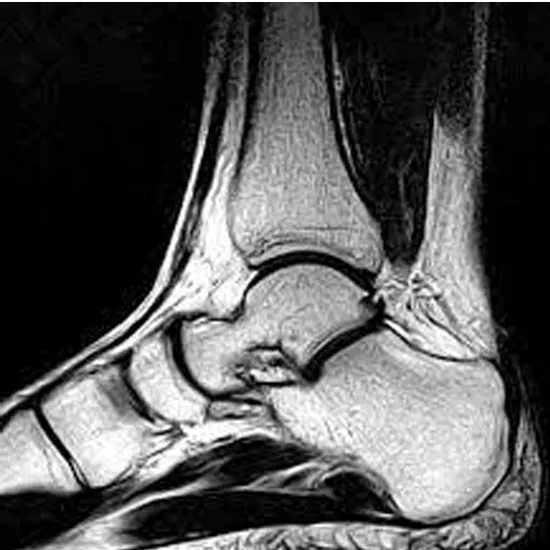

Left Ankle Joint MRI depicts bones, tendons, ligaments, muscles, and blood vessels.

Ankle injuries are often diagnosed using an MRI. An MRI of the left ankle joint identifies damaged or fractured ankle bones and soft tissue lesions, including ligaments, tendons, and muscles.